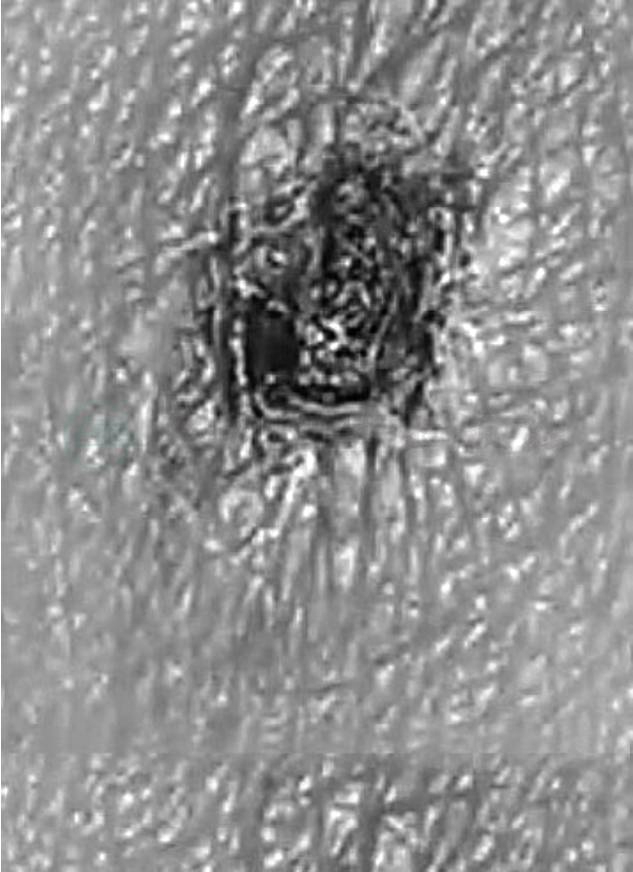

入院后予抗感染、补液、维持水电解质平衡、止泻等治疗。患者仍有发热,体温最高39.3℃。复查血常规:PLT 60.9×109/L;肝功能:ALT 143IU/L,AST 170IU/L,血气:pH 7.485,PCO2 3.29kPa。大便培养物无阳性发现。患者经过治疗后非但原有症状没有好转,而且还有转氨酶升高、体温升高等病情加重趋势。是否为急性病毒肝炎?抽血化验了各型病毒性肝炎抗体均阴性。患者经过治疗后基本已无腹泻,目前变成了发热、肝功能损害及血小板降低待查。能够造成这种情况的要考虑感染、血液系统疾病及自身免疫系统疾病。感染中立克次体感染、黑热病、布氏杆菌病等均有可能;血液病中白血病、恶性组织细胞增生症、淋巴瘤;自身免疫系统病中的系统性红斑狼疮、干燥综合征等也不能完全排除。在骨髓穿刺及自身免疫抗体结果回报无阳性发现后我们再次把重点放在了感染上。但是患者肥达、外斐试验均阴性,也无其他疫区接触史。似乎诊断走到了死胡同。所以我们只能重新仔细回顾病史并仔细体格检查:我们在患者右侧腋窝触到一个稍大的淋巴结,表面光滑、有轻压痛,可滑动。遂仔细检查全身皮肤并发现了一个黑色焦痂(见图1)。同时患者也回忆起发病前10天曾到野外游玩。我们马上复查了外斐试验:变形杆菌OXK凝集试验(OXK)1∶160。遂给予氯霉素治疗,同时加强护肝、维持水、电解质平衡及对症支持,4天后患者体温降至正常。1周后复查血常规:WBC 4.74×109/L,N 1.96×109/L,Hb 100g/L,PLT 90×109/L;肝功能:Alb 30.5g/L,ALT 47IU/L,AST 35IU/L。

图1 皮肤检查

我们从恙虫病的诊断标准中不难看出,早期诊断恙虫病最特征性的提示就是焦痂。恙虫病的焦痂特点:一般可见于腰部、胸部、腹部、腹股沟、会阴、肛门、腋窝等处,大小约0.5~3cm,焦痂表面干燥,周围皮肤可见环形红晕,不伴疼痛及瘙痒。这也从另一方面提示我们在疑难病例的体格检查过程中一定要细心、仔细。